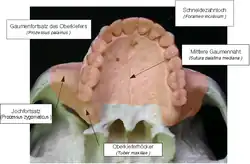

- Abriss des Tuber maxillae (Dessen Lage siehe Abbildung)